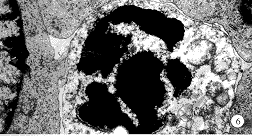

2.2 DC对诱导LPAK细胞的杀伤模式 对照组B组的BEL-7402细胞微绒毛丰富,细胞核大而圆,染色质分散,细胞质电子密度较低(图2). 实验组L-4和L-7大组中,不仅在DC与LPAK,LPAK与BEL-7402细胞之间,而且在DC与BEL-7402细胞之间都存在着细胞突起与微绒毛、或微绒毛与微绒毛的犬牙状交错接触(图3,4). 在L4组和LD4组中,BEL-7402细胞呈现不同程度的变性坏死. 细胞膜破裂,细胞轮廓不清,细胞肿胀;细胞核形态不一,有的核肿胀,有的核固缩;细胞质内细胞器明显破坏,内质网扩张,线粒体肿胀、嵴溶解消失,并可见髓鞘样小体(图5). L4组和LD4组的坏死细胞在形态上无明显差别. 在L7组和LD7组中,BEL-7402细胞则呈现不同程度的凋亡改变. 凋亡细胞的形态多样,有典型的改变,如细胞膜微绒毛消失;细胞核移位,染色质或凝聚、浓缩成新月形、弧形边集于核膜下,或固缩成团块状,或碎裂成小块、碎块被内质网包裹形成自噬体;细胞质浓缩,线粒体皱缩变小;浓缩的细胞碎片还向细胞外出芽隆起形成凋亡小体等. 也有不典型的改变,如细胞核核膜虽于核孔处断裂,但核染色质浓缩边集形成“菜花状”;细胞质内肿胀的线粒体中,有的内含致密体,有的嵴紊乱、断裂、甚至空泡化,但遗留嵴的痕迹;内质网或增生肥大,或出现不同程度的退行性变,甚至肿胀空泡化;而细胞器界膜和细胞膜一般保持完好(图6,7). L7组和LD7组的凋亡细胞在形态上无明显差别.

图6 L7组BEL-7402细胞呈明显的凋亡改变. ×5000

图7 LD7组BEL-7402细胞呈明显的凋亡改变. ×10000